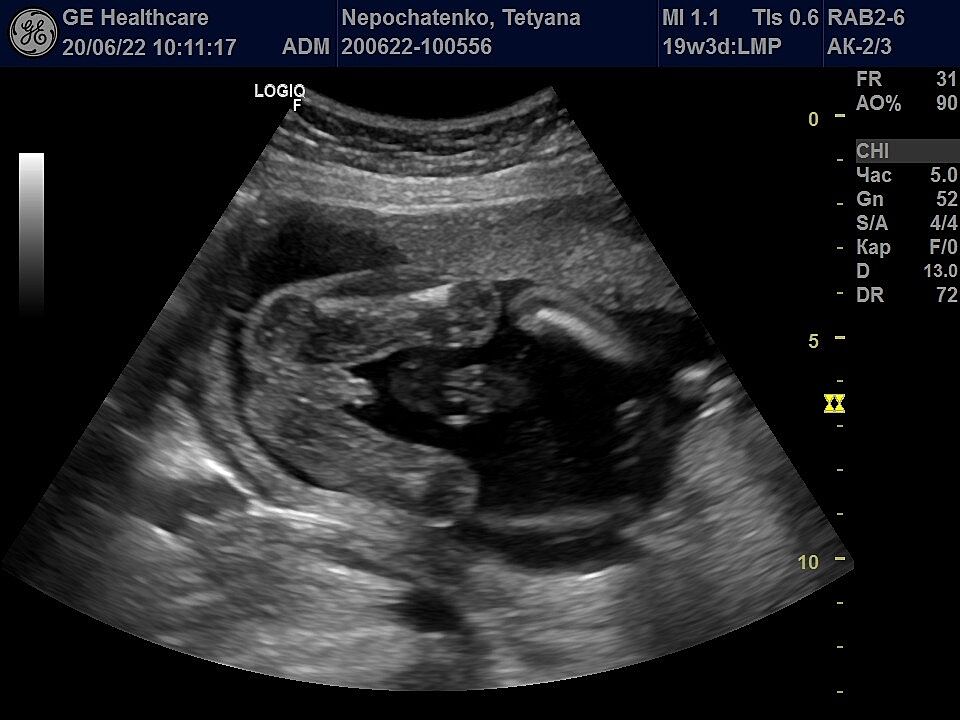

Дівчата, кого ви бачите?) Дівчинка чи хлопчик?)

Там немає голови )) ракурс жопка і ніжки )))

Боже, які гарні чоловічі принади)) ракурс схожий, тому думаю було б видно хоча б щось, а в мене все гладенько ))))

В мене такий самий знімок є . В автора точно дівчинка . А ще такий , нічого не розумію в ньому , але лікар сказав піпка

Ну по голівці наврядче визначать стать)) це між ніжками фото зробив лікар)))